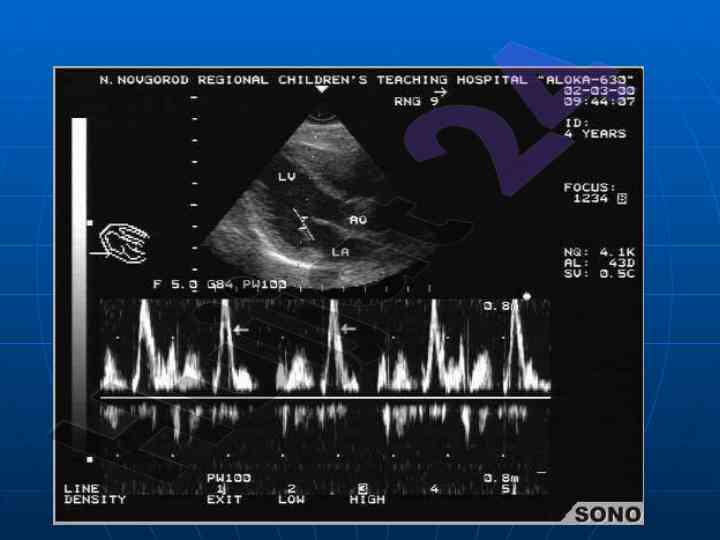

Ushbu maqolada yurak va qon-tomir kasalliklarining nurlanish tashxisi bo'yicha ma'lumotlar keltiriladi. U echokardiofragiya va angiografiya usullarini o'z ichiga oladi. Maqola universitetning tibbiy fakultet talabalariga yo'naltirilgan.